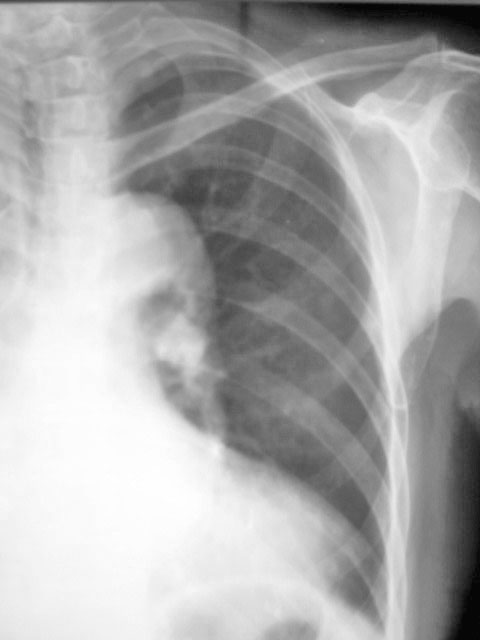

以下是引用影像之剑在2010-6-3 22:56:00的发言:[br]右侧胸廓塌陷,胸膜增厚。右侧肺野透光度减低,右肺门影增大,似可见模糊块影。右膈面不清,右肋膈角消失。左肺透光度增高,肺内未见明显实质性病变。心影主动脉弓部突出,肺动脉段凹陷,左心缘向左下扩大。左膈清。[br][br]考虑右侧胸膜增厚,胸腔积液,右肺膨胀不全。右肺门模糊块影,建议ct。左肺代偿性气肿。主动脉型心。

以下是引用吴医师在2010-6-3 23:59:00的发言:[br]请与老片对比。如大致相同,考虑胸膜肥厚。如有明显不同,请ct检查。